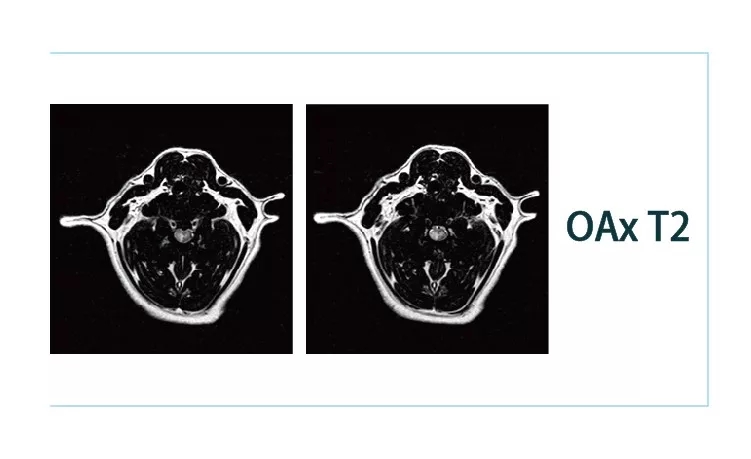

640.webp (2).jpg